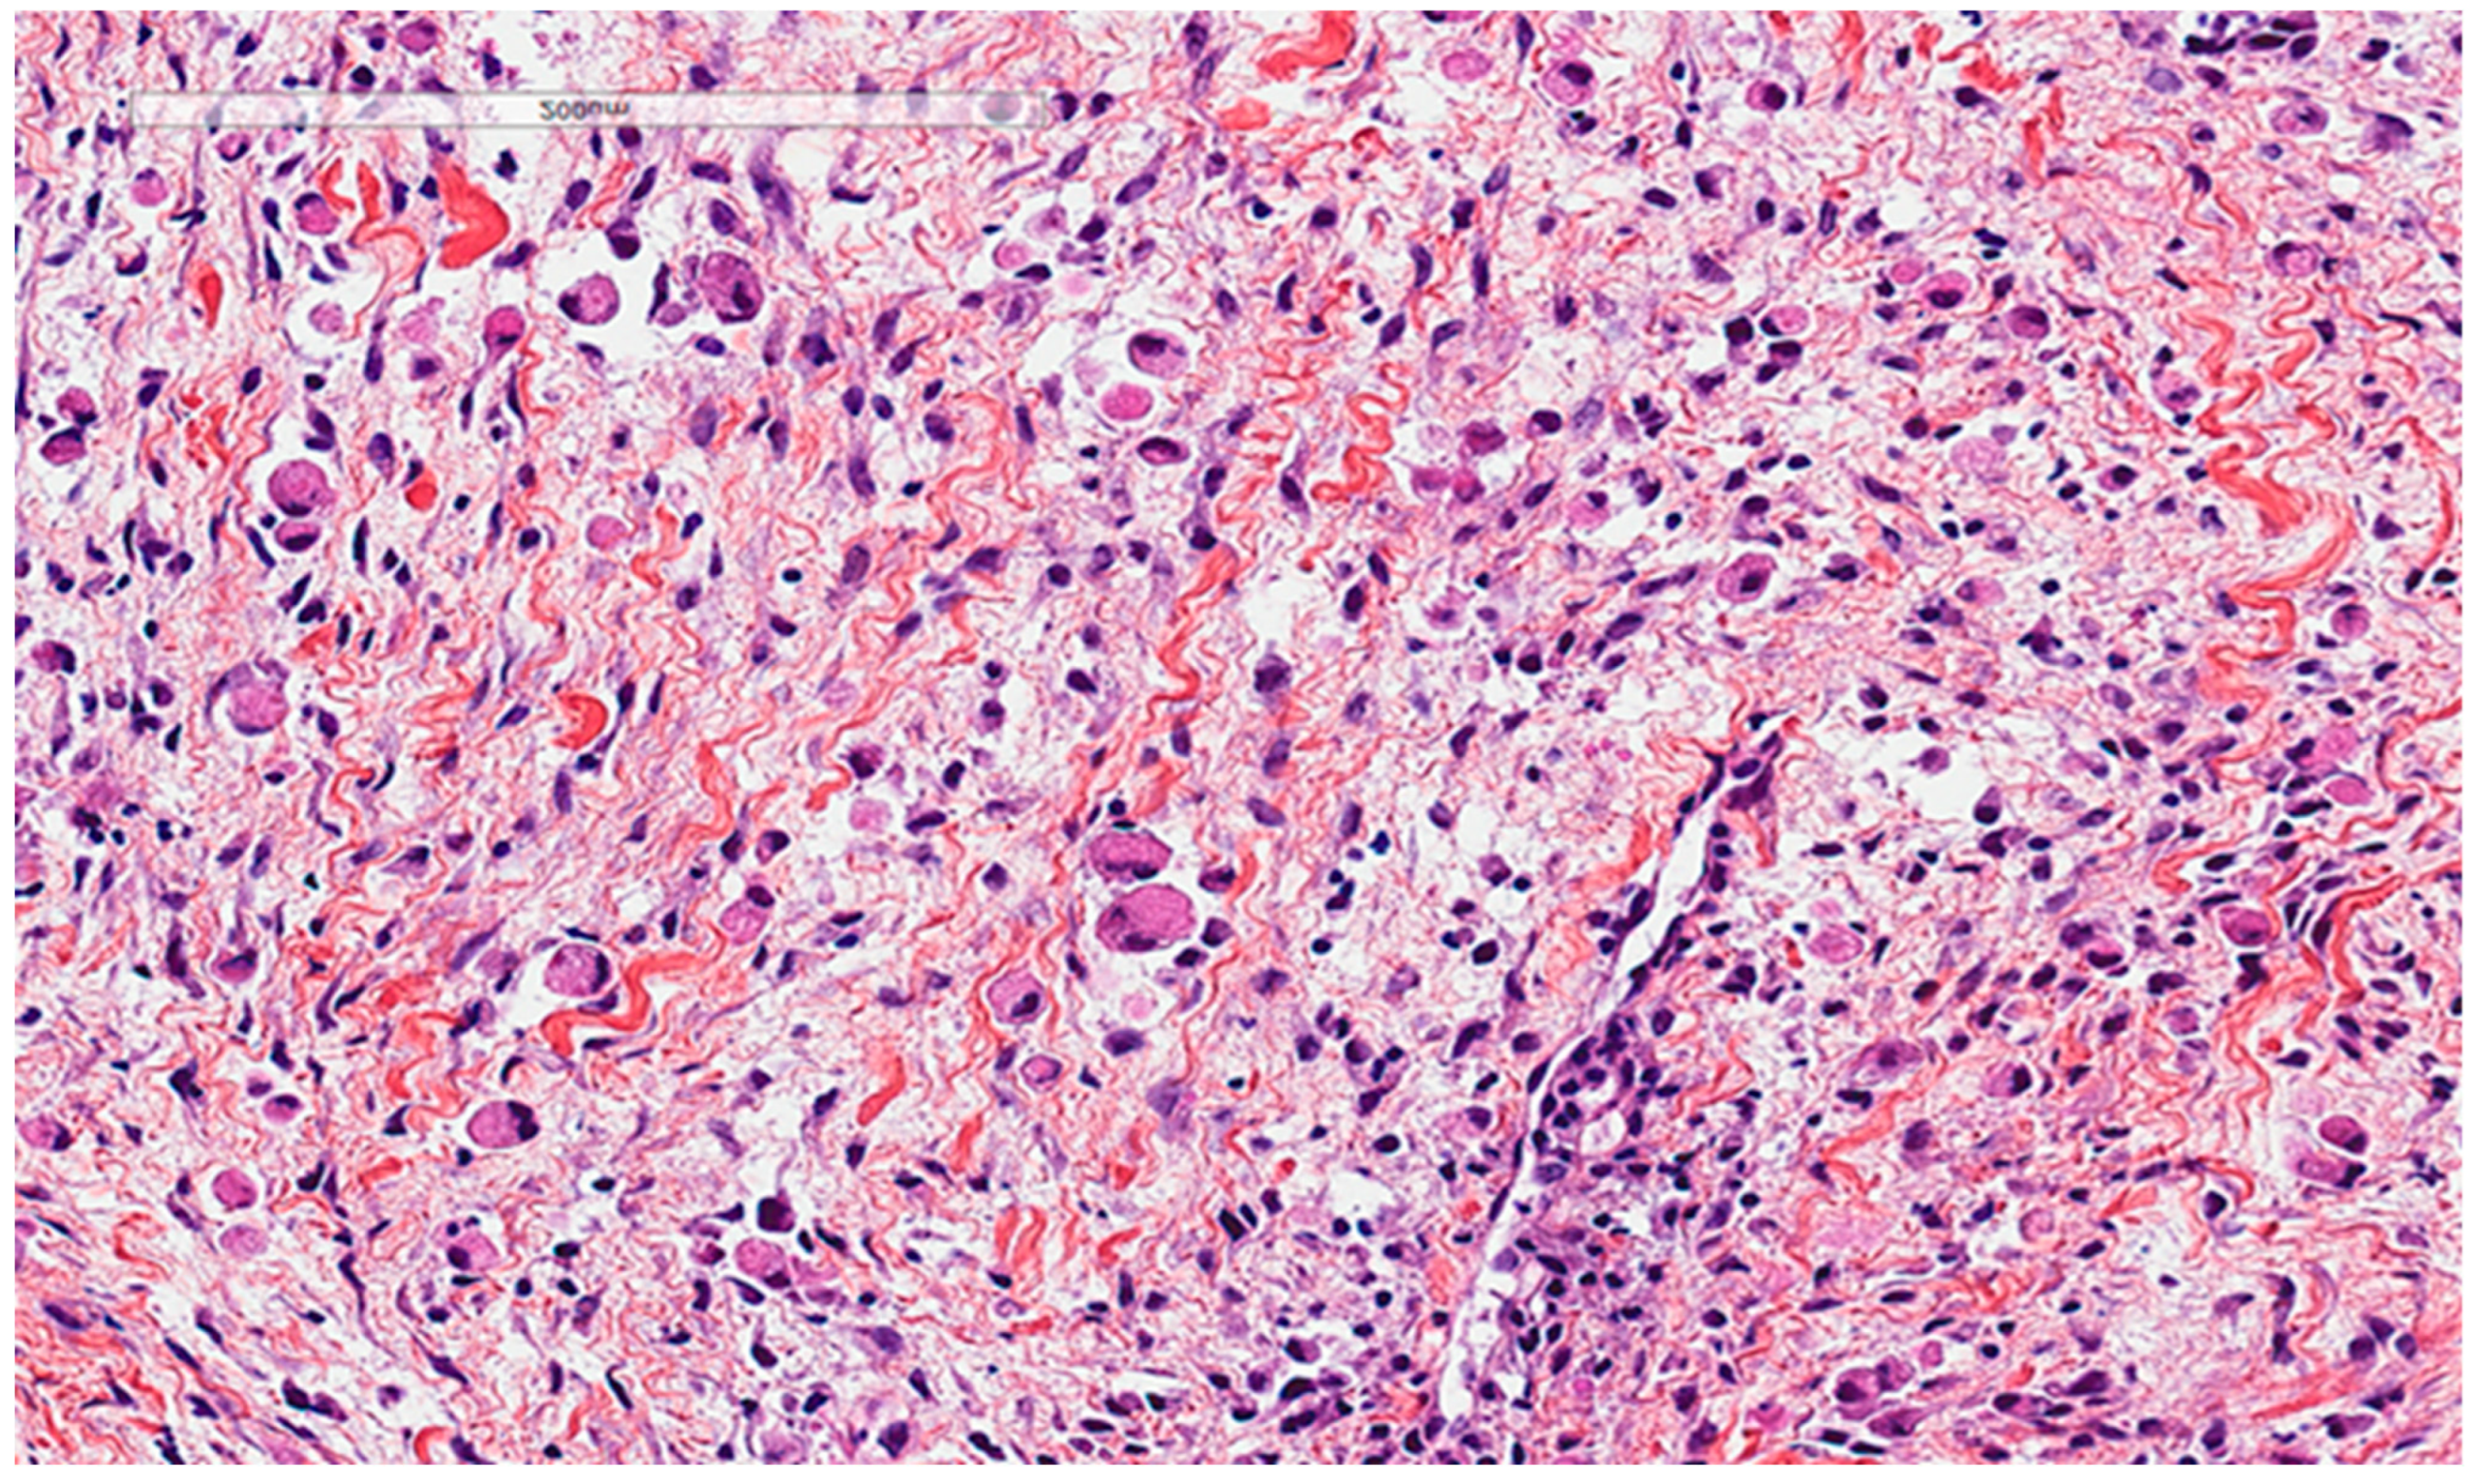

Figure 7. Gaucher disease. (A). Bone marrow involvement, with histiocytes with an eosinophilic cytoplasm (Gaucher cells). (B). PAS-positive histiocytes. (C). CD68-positive histiocytes. The patient, a 52-year-old female, suffered from hepatosplenomegaly and anemia.

Gaucher disease, an autosomal recessive lysosomal storage disease, is characterized by the macrophagic accumulation of glucocerebroside affecting many organs, especially the liver, spleen, and bone marrow. It is due to an enzymatic defect, producing histologically the so-called crinkled-paper eosinophilic cytoplasm (Figure 7). In addition, some diseases, such as chronic myelogenous leukemia, can show bone marrow cells with similar morphological findings, called pseudo-Gaucher cells; based on that, some authors described crystal-storing histiocytosis as containing pseudo-pseudo-Gaucher cells (44). In the stomach, Russel body gastritis is considered an important pitfall of gastric crystal-storing histiocytosis, as both can be associated with H. pylori gastritis. The principal histological feature of Russel body gastritis is the presence of accumulated polyclonal homogenous round deposits of immunoglobulins within plasma cells cytoplasm, which are positive for anti-CD138. In addition iron pill-induced gastritis or duodenitis can present with histiocytic brown crystalloid-like material with iron-stain positivity (Figure 8). In the duodenum, the histiocytic accumulation in the lamina propria in Whipple disease can be a pitfall of crystal-storing histiocytosis. These histiocytes are consistently PAS-positive (Figure 9). In addition, amyloidosis could make a differential diagnosis of crystal-storing histiocytosis, given that the material is pale pink, glassy, and amorphous; however, it is extracellular, mostly vascular and perivascular, and produces a birefringent apple-green color under polarized light (Figure 10).